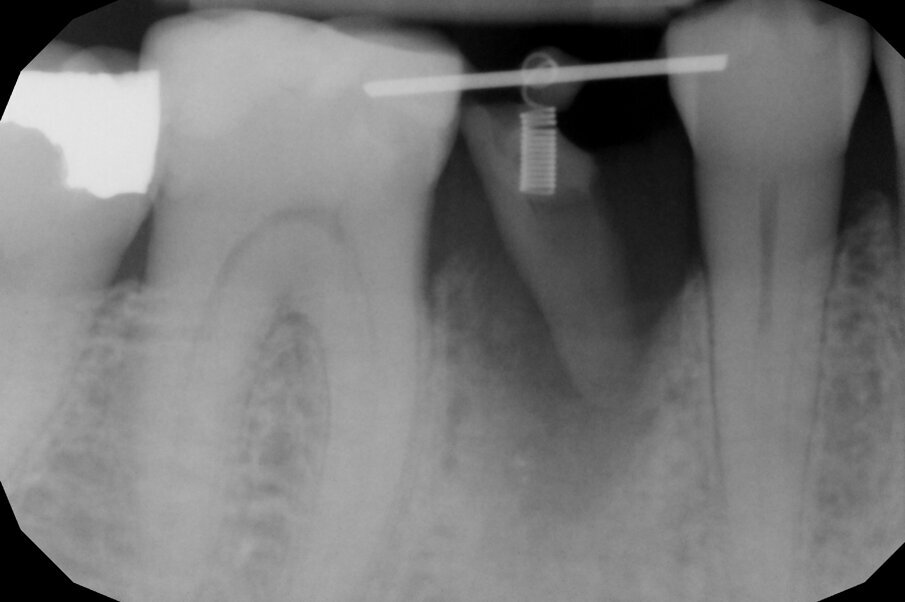

Per ottenere questo risultato nel gennaio 2021 è stato ancorato un segmento di arco in acciaio a sezione quadrata 0.021” x 0.025” agli elementi 4.4 e 4.6 per mezzo di composito. Il segmento è servito da ancoraggio per una molla con forza di trazione 150 g in posizione obliqua in senso disto-mesiale.

L’estrusione completa del frammento ha richiesto un tempo di 6 mesi, durante i quali è stata modificata più volte l’inclinazione della molla per evitare che il movimento diventasse ortogonale al segmento e mantenere la traiettoria prevista. Così facendo, è stato possibile rigenerare naturalmente l’intero alveolo e inserire, dopo 3 mesi di ulteriore maturazione del tessuto, in un contesto osseo ideale e perfettamente rigenerato un impianto Syra (Sweden & Martina) di diametro 4.25 mm e lungo 11 mm.